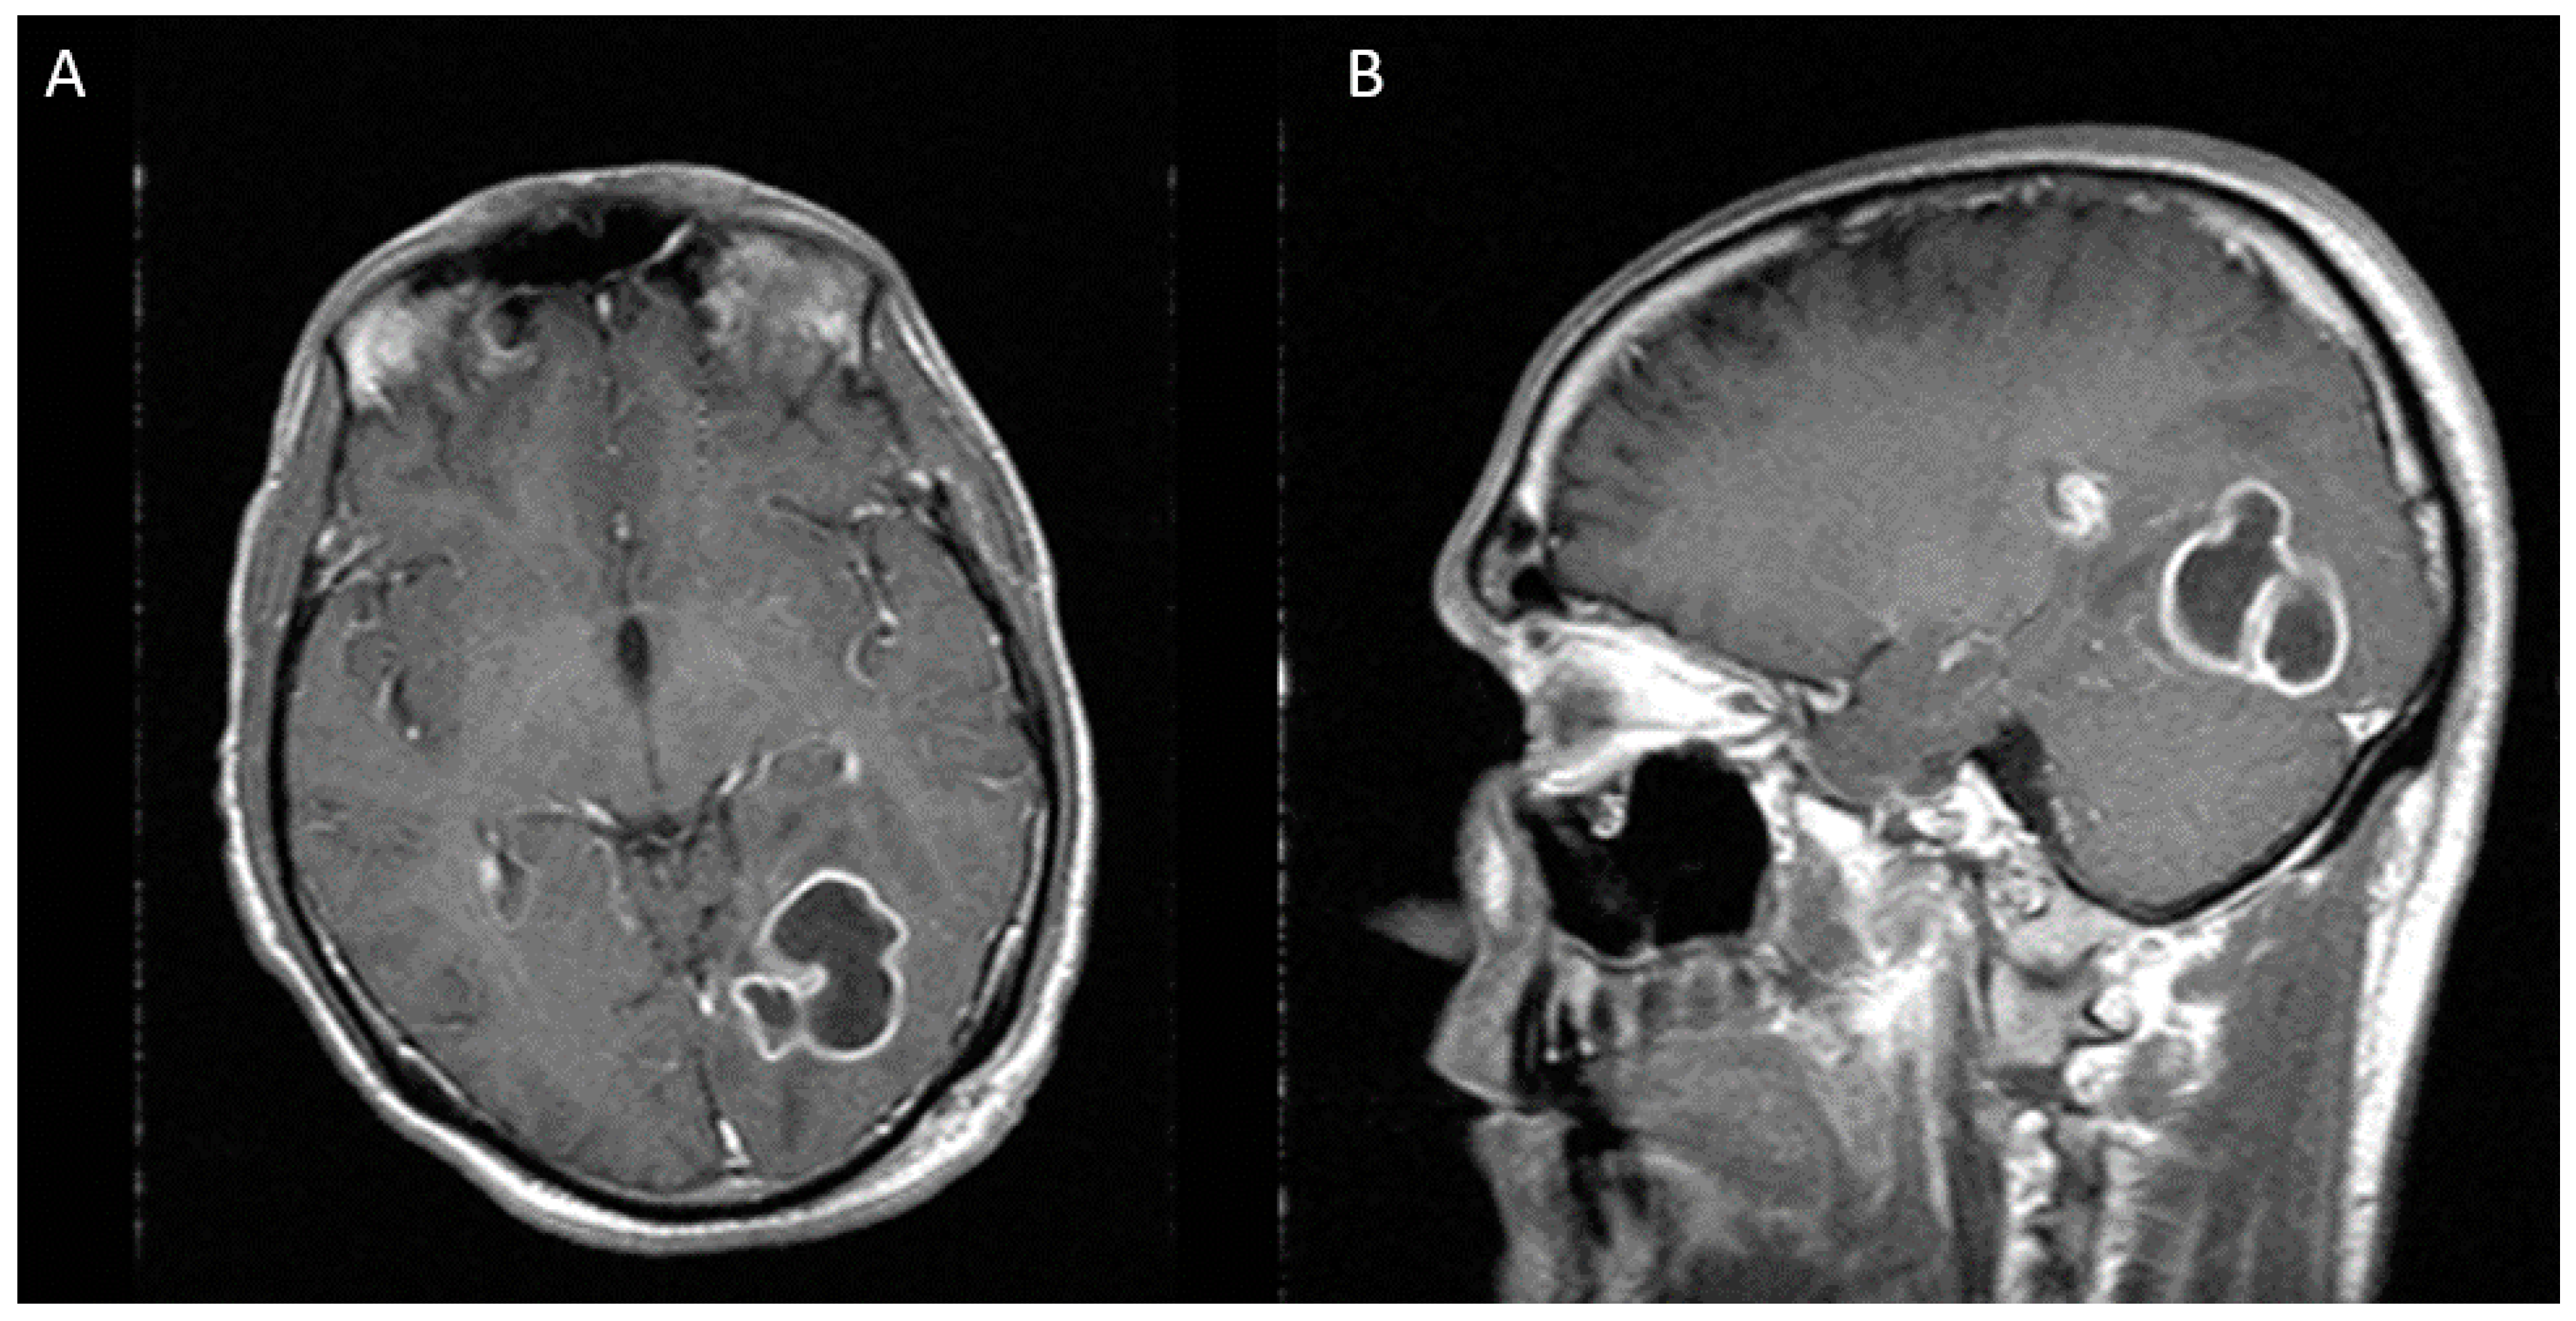

Cureus Cerebral Abscess Due to Nocardia beijingensis Associated With HIV Case Report and Mini

From www.cureus.com

Cureus Cerebral Abscess Due to Nocardia beijingensis Associated With HIV Case Report and Mini Brain Abscess Aids  An abscess can also keep blood from flowing to parts of your brain.   how is a brain abscess treated?  cerebellar or brain stem abscesses are often indication for posterior fossa craniotomy due to the high risk of brain herniation.[3,25]. A brain abscess is a medical emergency that requires immediate attention.   nocardia is an important cause of brain. Brain Abscess Aids.

From www.researchgate.net

(PDF) Cerebral Abscess Due to Nocardia beijingensis Associated With HIV Case Report and Mini Review Brain Abscess Aids    the diagnosis of brain abscess requires a high index of suspicion since it can have a subtle presentation.   how is a brain abscess treated?   clinical signs of increased intracranial pressure (eg, papilledema, cushing triad [hypertension, bradycardia, and irregular.   the diagnostic approach to a patient with hiv/aids and a brain mass should be stepwise, considering host factors,.. Brain Abscess Aids.